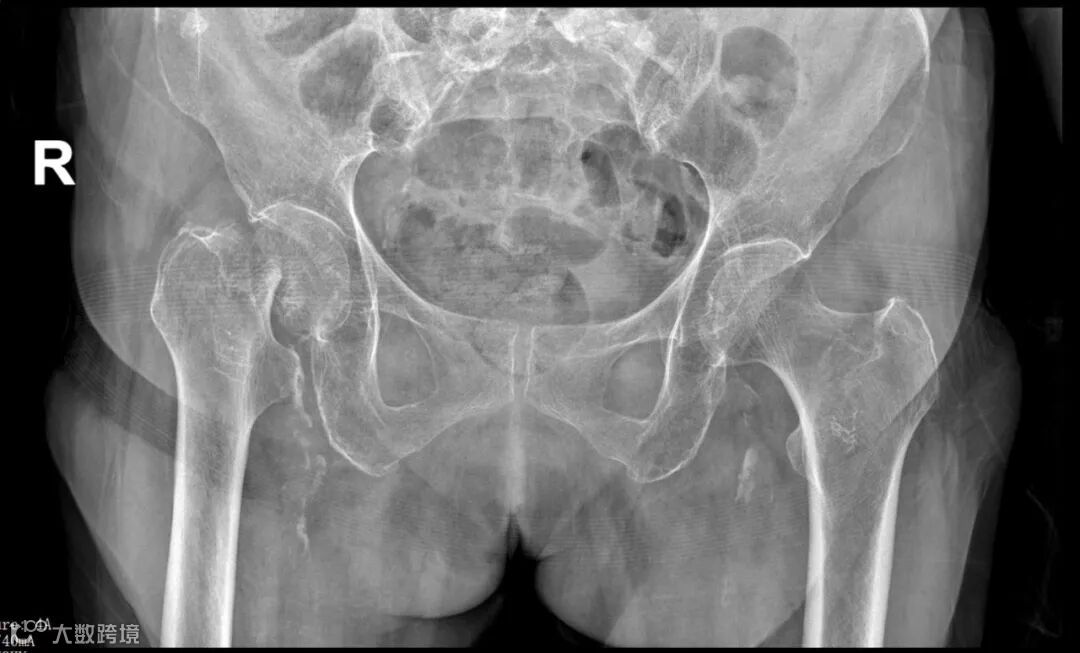

2月27日下午4时许,北海91岁的石奶奶走路不慎跌倒,右髋关节剧烈疼痛,不能自行站立,在外院就医诊断为“右股骨颈骨折”,5个小时后转到市人民医院关节脊柱骨科住院治疗。